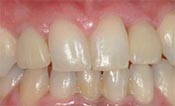

安卓健临床案例分享

安卓健种植产品销往全球100多个国家精密工程CFDA

权威认证,可放心使用。安卓健种植体手术程序简单,

更少创伤,更快恢复,更加安心。